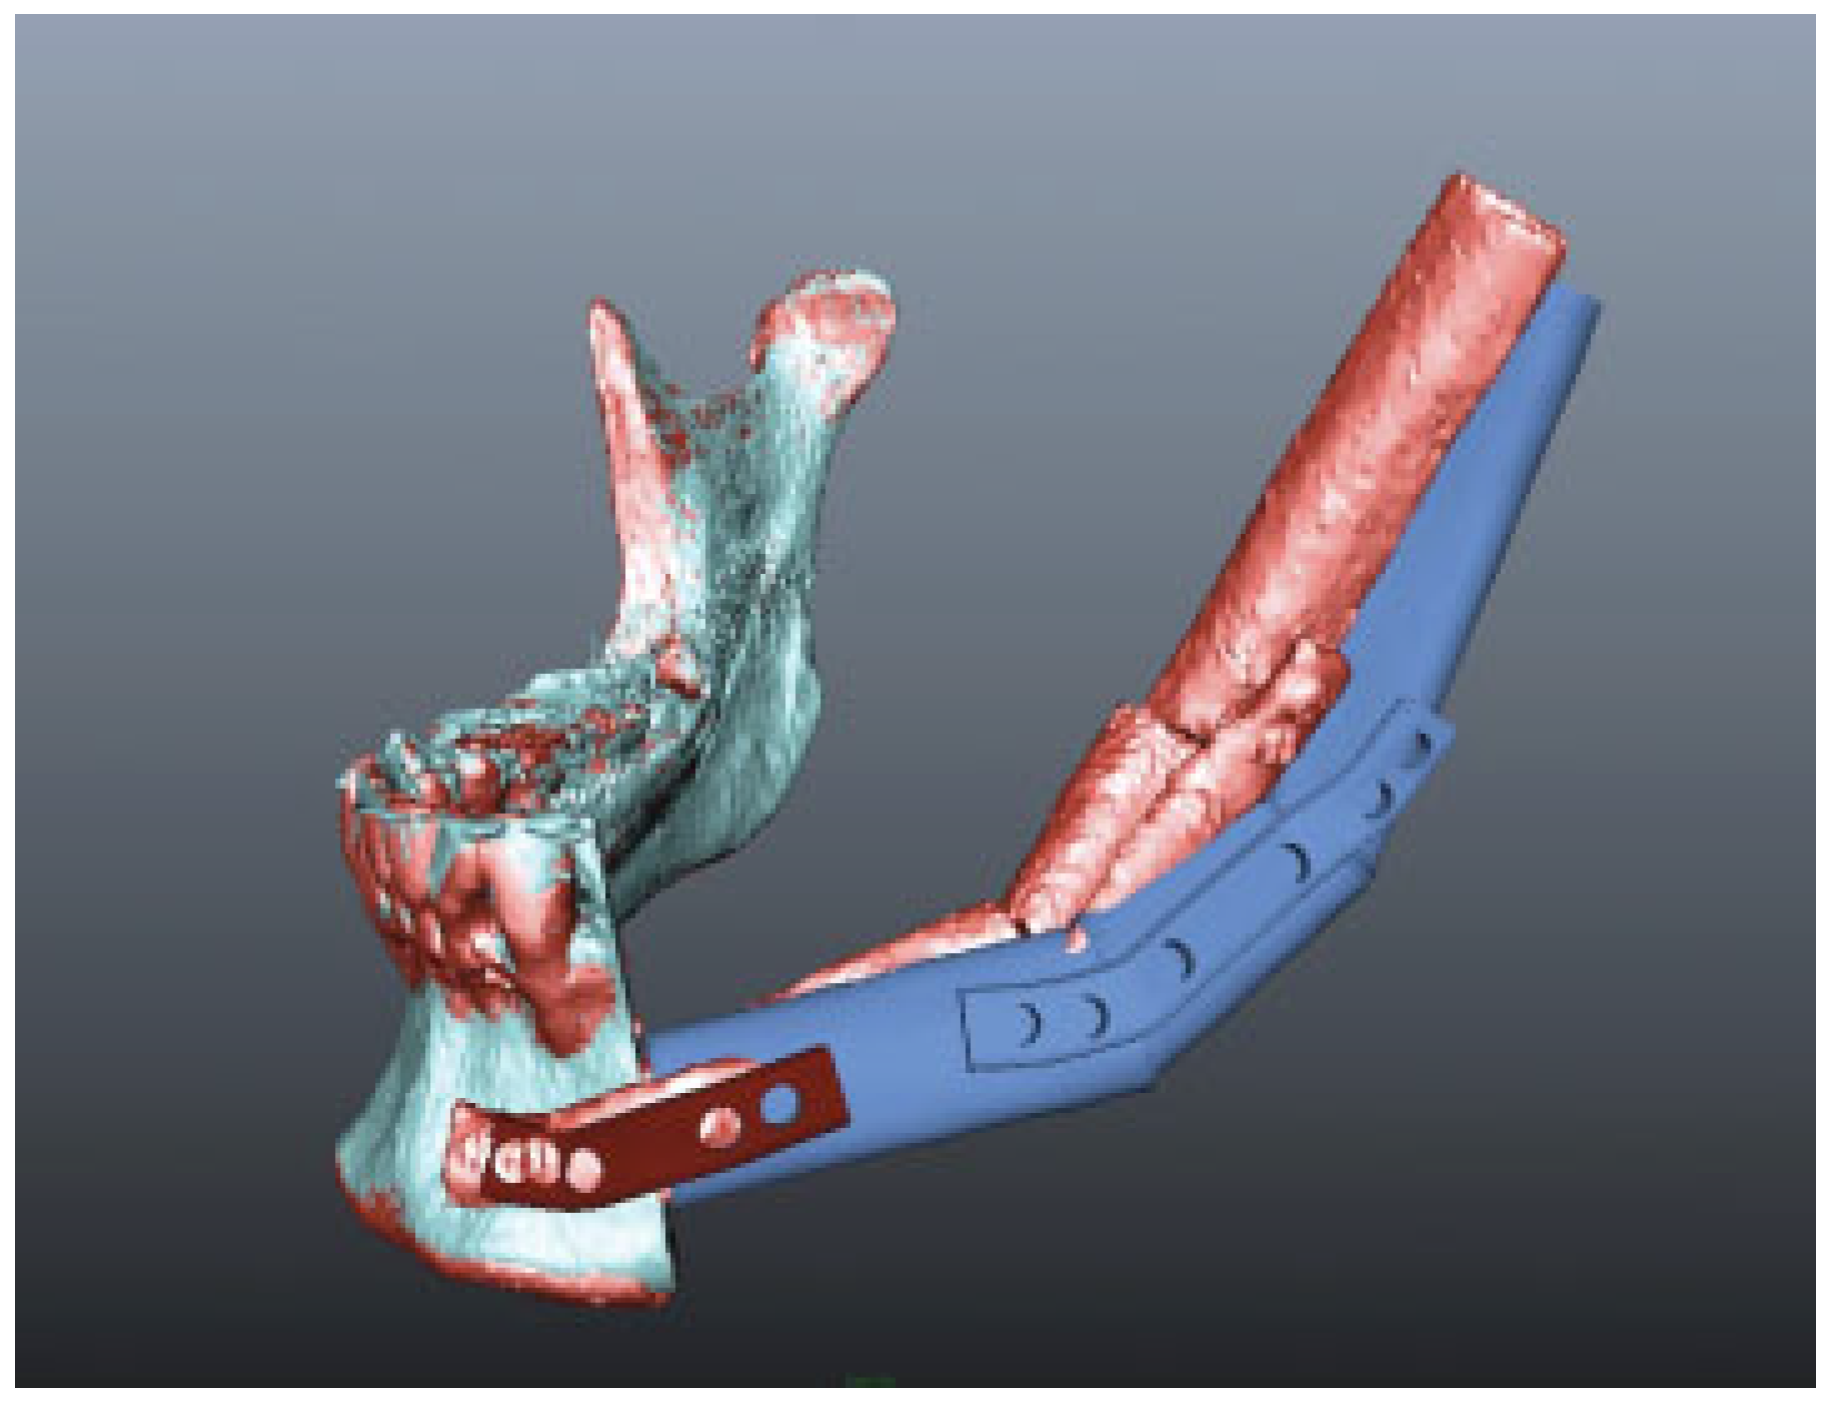

The additive manufacturing method EBM produces custom-designed implants fully usable under clinical conditions in reconstruction of acquired defects in the mandible with good agreement between the treatment plan and the fit as demonstrated during operation (Figure 4 and Figure 5) and the subsequent short-term clinical as well as the superimposed preoperative treatment plan with the radiological outcome (Figure 6). Clinically, the custom-made cutting guide, mesh, and the load-bearing reconstruction plates were appreciated during surgery as the implants were easy to handle, fixate, and reduced operating time significantly.

Figure 6. Difference between the preoperative treatment plan and treatment outcome. Dark blue is the preoperative treatment plan. Red being the postoperative treatment outcome.